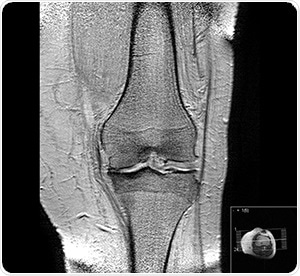

"Gonarthrosis, medial abuse of cartilage" by Scuba-limp [GFDL, CC-BY-SA-3.0 or CC BY-SA 2.5],

via Wikimedia Commons

The study explored numerous significant parameters of bone integrity in bone samples collected from human cadavers. The main parameters were subchondral bone plate thickness, bone mineral density and structural model index that were measured using near-infrared spectroscopy. A dual channel Avantes system combined with the AvaSpec-ULS2048L with the high-sensitivity AvaSpec-NIR256-2.5-HSC was used to record the NIR spectral data.

Spectra were recorded across three wavelength series already recognized for penetrative capabilities in living tissue. This is called the biologic or therapeutic optical window. Firstly, the window covered the range 650-950 nm, then, from 1100-1350 nm, and lastly, the biologic window studied was 1600-1870 nm. This data was correlated against micro-computed tomography results of the same bone samples using partial least squares regression multivariate technique.

Findings showed that an important role was played in the relationship between optical response and subchondral bone properties due to the wavelength-dependent penetration of light into osteochondral samples. The strongest correlation and lowest error rate against the tomography results was identified in the first optial window; λ 650-950 nm. This presents the highest potential for adaptation into arthroscopy standards of care.